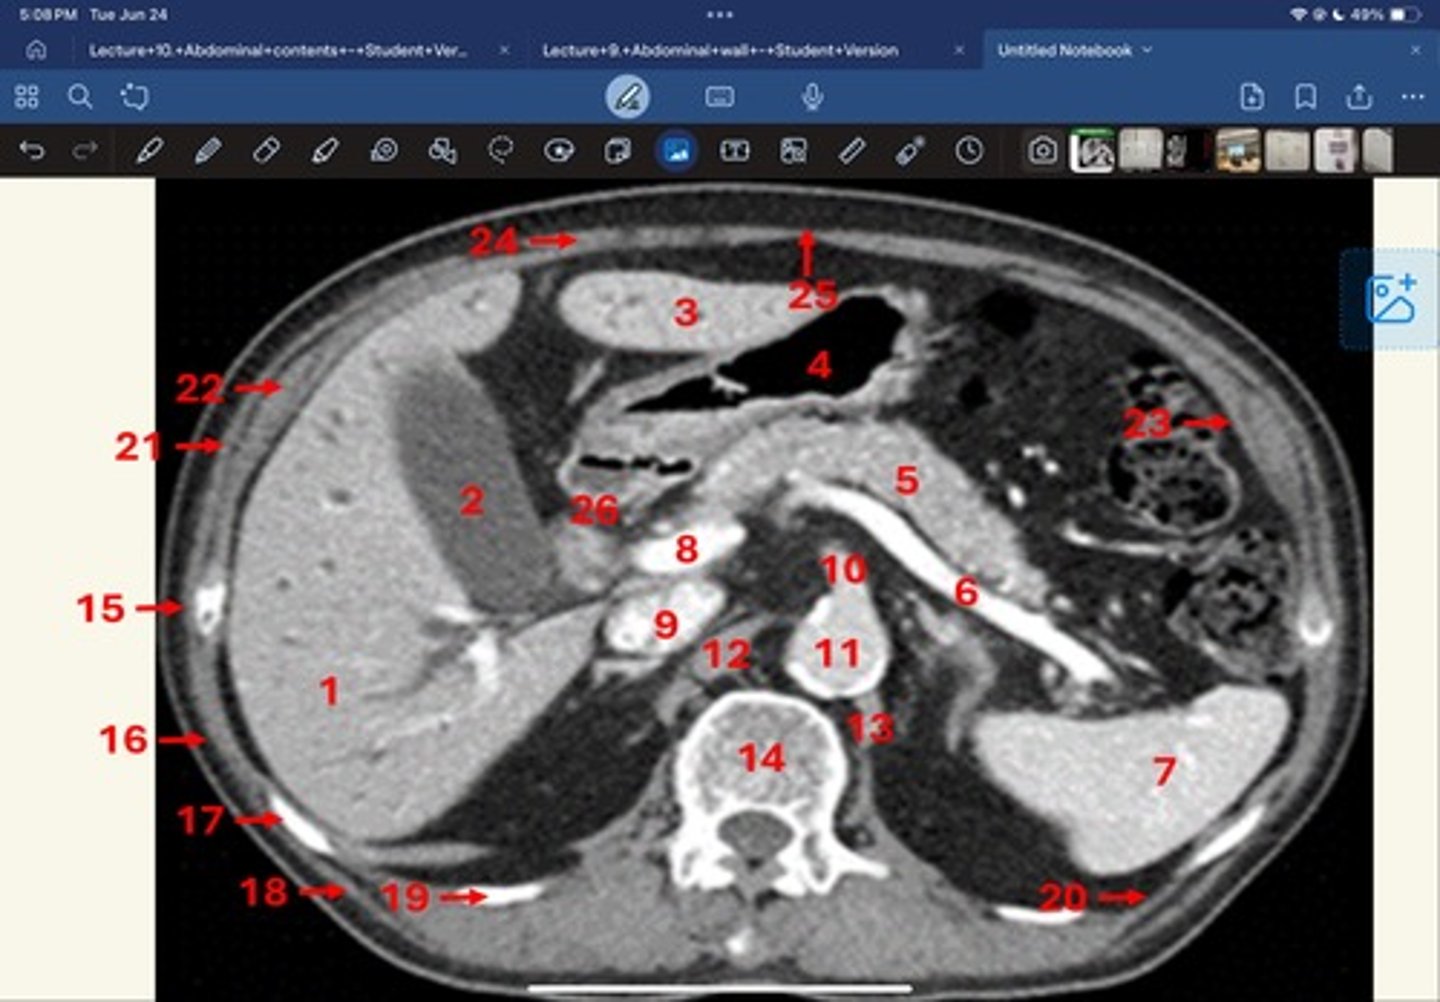

Right lobe of liver

What is 1

Gallbladder

What is 2

Left lobe of liver

What is 3

Stomach, pylorus

What is 4

Pancreas

What's 5

Splenic vein

What's 6

Spleen

What's 7

superior mesenteric vein

What's 8

Inferior vena cava

What's 9